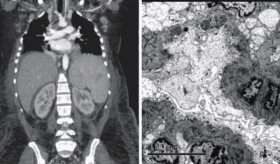

Por esta razón, el Instituto Nacional de Salud y el Departamento de Oncología han impulsado estudios comparativos sobre la efectividad de radiografías y tomografías computarizadas (CT scan) en la detección temprana. Los resultados han demostrado que, en grupos de riesgo, el uso de CT scan permite identificar el cáncer en etapas iniciales, aumentando las oportunidades de tratamiento y curación.

El pulmonólogo explicó que el seguimiento con radiografías de tórax no es la opción más adecuada para detectar cáncer de pulmón en pacientes de alto riesgo. En su lugar, recomienda la tomografía computarizada (CT scan) de baja dosis, especialmente en personas con más de 20 años fumando una caja de cigarrillos al día o en exfumadores que dejaron el hábito hace menos de 15 años. Este método ha demostrado ser eficaz en la detección temprana de la enfermedad, lo que aumenta las posibilidades de un tratamiento exitoso.

En Puerto Rico, existen varios centros que realizan tomografías computarizadas de baja dosis para la detección temprana del cáncer de pulmón. Sin embargo, en pacientes con antecedentes de exposición significativa y síntomas como tos persistente, hemoptisis o dificultad para respirar, así como en aquellos con enfermedades respiratorias crónicas, podría ser más adecuado realizar una tomografía convencional. Aunque este método implica una mayor exposición a la radiación, permite identificar hallazgos específicos que pueden ser clave para el diagnóstico.